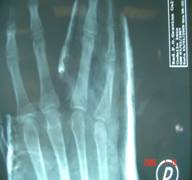

La sintesi rigida deve essere scelta quando le condizioni cliniche lo permettono, ma anche quando si pensa ad una precoce mobilizzazione della falange, per evitare fenomeni aderenziali. Deve essere ricordato, prima della scelta dell’approccio chirurgico, che la stabilità della frattura risente in maniera diretta del grado di energia del trauma: traumi a bassa energia determinano infatti fratture spesso stabili, con integrità del periostio e dei tessuti molli circostanti, mentre traumi in cui le componenti energetiche siano bi o tridirezionali piuttosto che ad alta energia, determinano spesso scomposizione delle fratture, complicanza nei tessuti molli e non integrità del periostio.